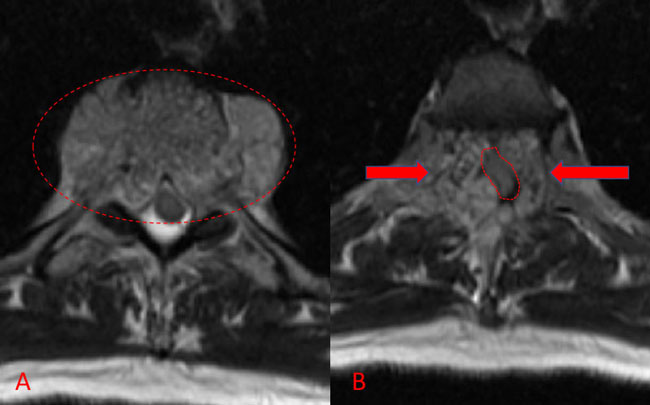

Figure 1. B and C) Axial MRI images of T3 demonstrates extensive infiltrative lesion with extradural compression of the thoracic spinal cord. (Dashed lines in A) tumor infiltration; Dashed lines and Arrows in B) cord compression.

He presented to the emergency room with one-week history of thoracic pain in addition to bilateral lower extremity weakness and paraparesis. MRI imaging with contrast showed a diffuse abnormal signal within the vertebral body of T3 and the posterior elements with lobulated soft tissue lesion extension into both paraspinal areas (Figure 1. A, B, C).